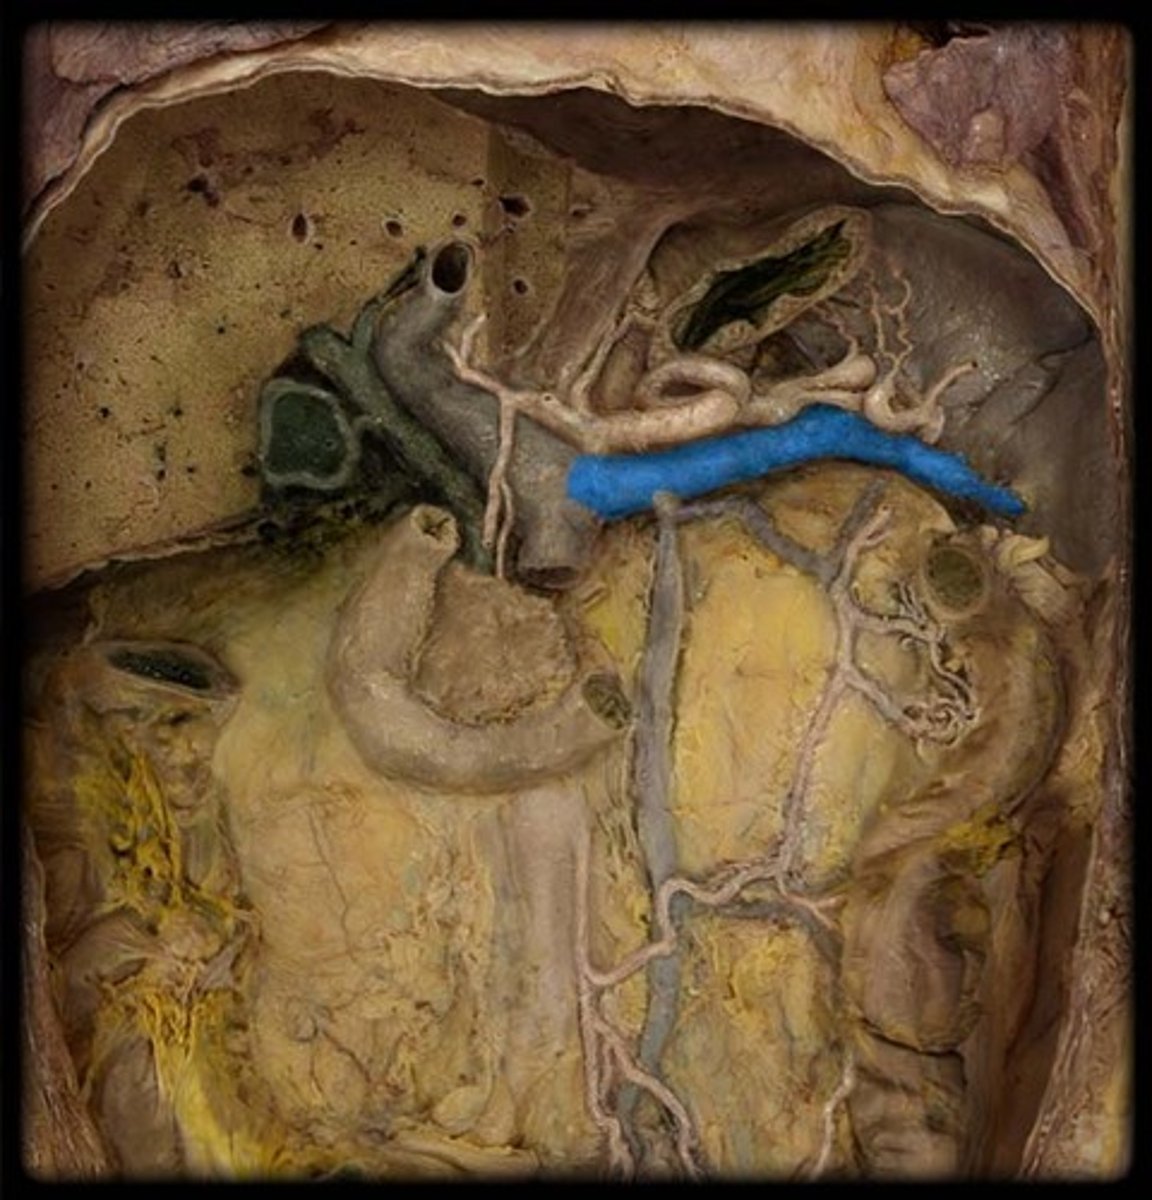

porta hepatis

where the blood and lymph vessels, bile ducts, and nerves enter and leave the liver

hepatic artery proper

right hepatic artery

left hepatic artery

cystic artery

common bile duct

common hepatic duct

cystic duct

hepatic portal vein

gallbladder

celiac trunk

splenic artery

common hepatic artery

hepatic artery proper

gastroduodenal artery